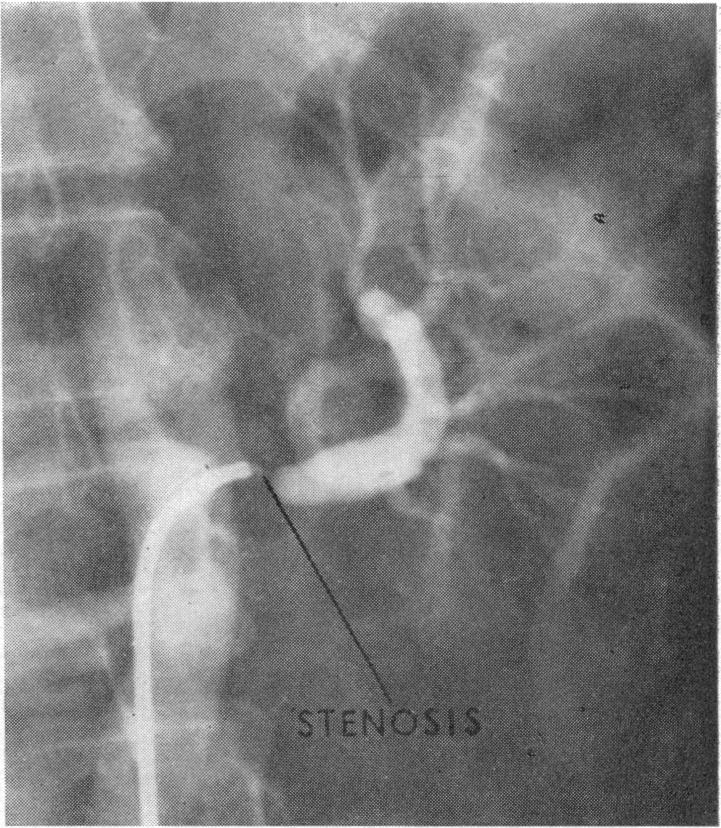

The diagnosis and treatment of renal-artery stenosis.

Br Med J. 1960 Jul 30;2(5195):327-38. doi: 10.1136/bmj.2.5195.327.